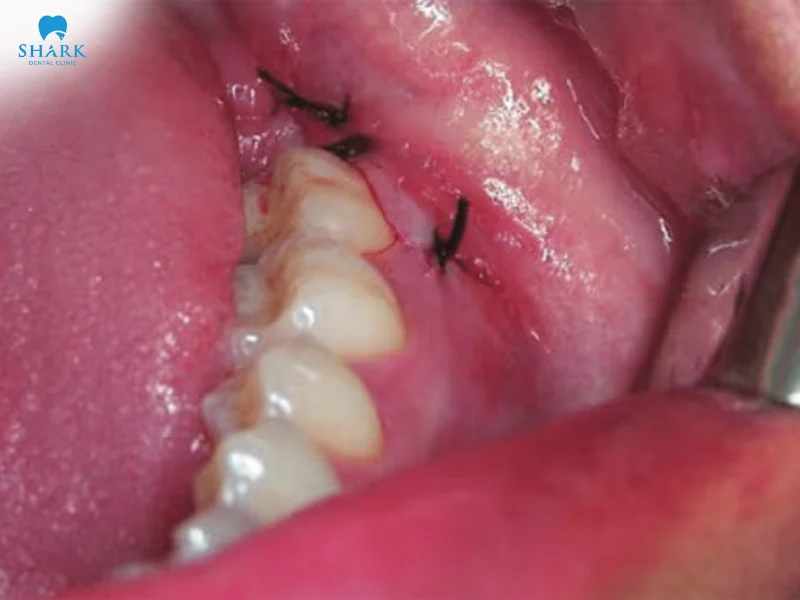

Trong trường hợp cần phải nhổ những chiếc răng khôn có kích thước lớn, chiếm nhiều diện tích trên khung hàm và răng khôn mọc ngang thì các bác sĩ cần phải khâu vết mổ lại mới có thể hoàn tất quy trình nhổ răng khôn.

Lúc này, bác sĩ có thể dùng chỉ thường hoặc là chỉ tự tiêu nha khoa để khâu vết mổ tùy theo nhu cầu của khách hàng.

Việc nhổ răng khôn khâu hoàn tất bằng chỉ tự tiêu nhằm mục đích ức chế tình trạng chảy máu nhiều do vết thương quá sâu hoặc là quá lớn, điều này còn hỗ trợ cho vết thương được nhanh chóng lành lại hơn.

Bên cạnh đó, sử dụng chỉ tự tiêu nhổ răng khôn còn có thể giúp cho bệnh nhân vệ sinh răng miệng và ăn uống một cách dễ dàng, vết mổ sẽ không bị tác động trực tiếp, cục máu đông trong ổ răng sẽ không bị làm tan ra.

Nhổ răng khôn bao lâu thì lành? Sau khi hoàn tất nhổ răng khôn và đã khâu chỉ tự tiêu, cục máu đông sẽ được hình thành trong ổ răng, tình trạng sưng mặt sẽ thuyên giảm nhanh chóng sau khoảng từ 2-3 ngày. Và trong khoảng 02 tuần tiếp theo đó, vết thương sẽ lành lại hoàn toàn.